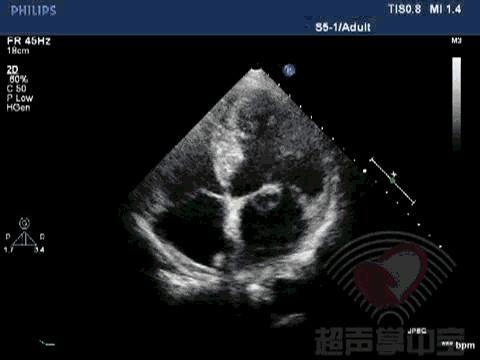

经典病例▏二尖瓣囊肿中竟然全是血液? 动态图2:四腔心切面显示该囊状物质软,有形变,二尖瓣开放正常